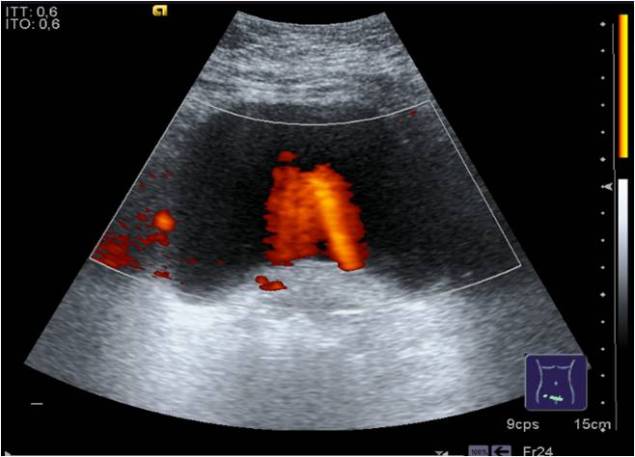

En Longitudinal, el Uréter derecho se alarga y busca su entrada en la vejiga, durante la exploración éstos pueden variar su tamaño al drenar la orina en la vejiga que puede estudiarse con Jet Ureteral que no es más que colocar el Doppler Color a la altura de la entrada de ambos uréteres en la vejiga y esperar a que la orina eyectada en la vejiga sea detectada por el Color como un flujo que nos representará en color dentro de la vejiga…eso certificará sin más que los uréteres están drenando su contenido, mira:

In Longitudinal, the right Ureter lengthens and looks for its entrance in the bladder, during the exploration these can vary their size when draining the urine in the bladder that can be studied with Ureteral Jet that is not more than to place the Color Doppler at the height of the entrance of both ureters in the bladder and wait for the urine ejected in the bladder to be detected by the Color as a flow that will represent us in color inside the bladder … that will certify without further ado that the ureters are draining their contents, look: